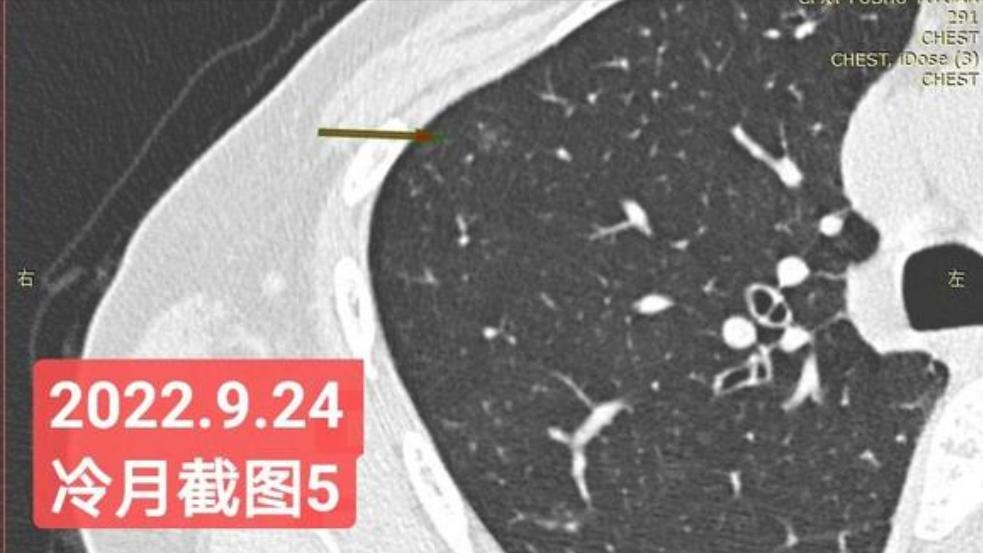

非常感谢戴主任和冷月等几位吧主的无私奉献,你们牺牲自己的休息时间,为广大患者排忧解难,你们对待病人,如同亲人一样,真的好感动!上次,在贴吧里咨询过戴主任关于我的肺结节情况,戴主任说,我右肺下叶那个结节高危。心里好害怕,距离上次CT间隔三个月,我又做了肺部CT,这次还要劳烦戴主任以及吧主们,帮我看看我的肺结节,严重吗?需要马上手术吗?

我昨天把我五次肺部CT电子版以及报告,发给了冷月吧主,昨天晚上,冷月吧主就为我截好图,发给我,非常令我感动,谢谢您冷月吧主,您辛苦了,您要多休息,不要太辛苦了。

我是21年7月做肺部CT,报告给报出0.5厘米肺结节。(但大夫说,20年就已经有那个肺结节了,因为小,报告没给报)。自发现肺结节后,吃了四个月中药,结节没有缩小,反而增大了。今年8月1日开始到现在,又吃了近两个月的蒙药了。 结节还是没有缩小,反而在增大。21年7月到现在,复查过3次肺部CT了。结节一直在增大。最近一次复查时间是2022年9月24日。

上次找戴主任贴吧咨询过,主任说我右肺下叶那个结节高危,距离上次CT,到现在三个月复查肺部CT。所以9月24日又复查做了肺部CT。

右下肺结节高危,肺窗已经到亚实性阶段CTR>0.5,纵膈窗可见实性,目前已经不属于异质混磨,而且PSN亚实性结节。